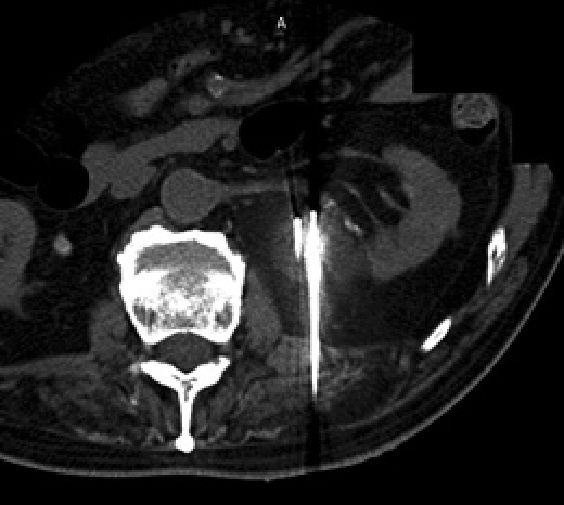

治療前

治療中

治療後

右腎臓の摘出後の患者さんで、左腎臓にがんができています。治療中では腫瘍が黒い部分で覆われており(赤い印で囲まれた範囲)、氷ができているのがわかります。治療後では腫瘍が壊死しているのがわかります。